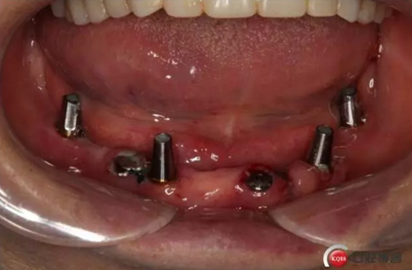

2)術(shù)前準(zhǔn)備及手術(shù)過(guò)程,測(cè)量血壓及血糖,簽種植知情同意書(shū);嚴(yán)格遵循無(wú)菌操作,局麻下采用微創(chuàng)技術(shù)于323436分別植入osstem4.0X10,4.0X10,4.5X7; 434446分別植入osstem4.0X1O,4.0X10,4.5X7.初期穩(wěn)定性均達(dá)到了35N.CM以上;嚴(yán)密縫合,止血,種植體位點(diǎn)和方向與設(shè)計(jì)一致。

健康的牙齦袖口